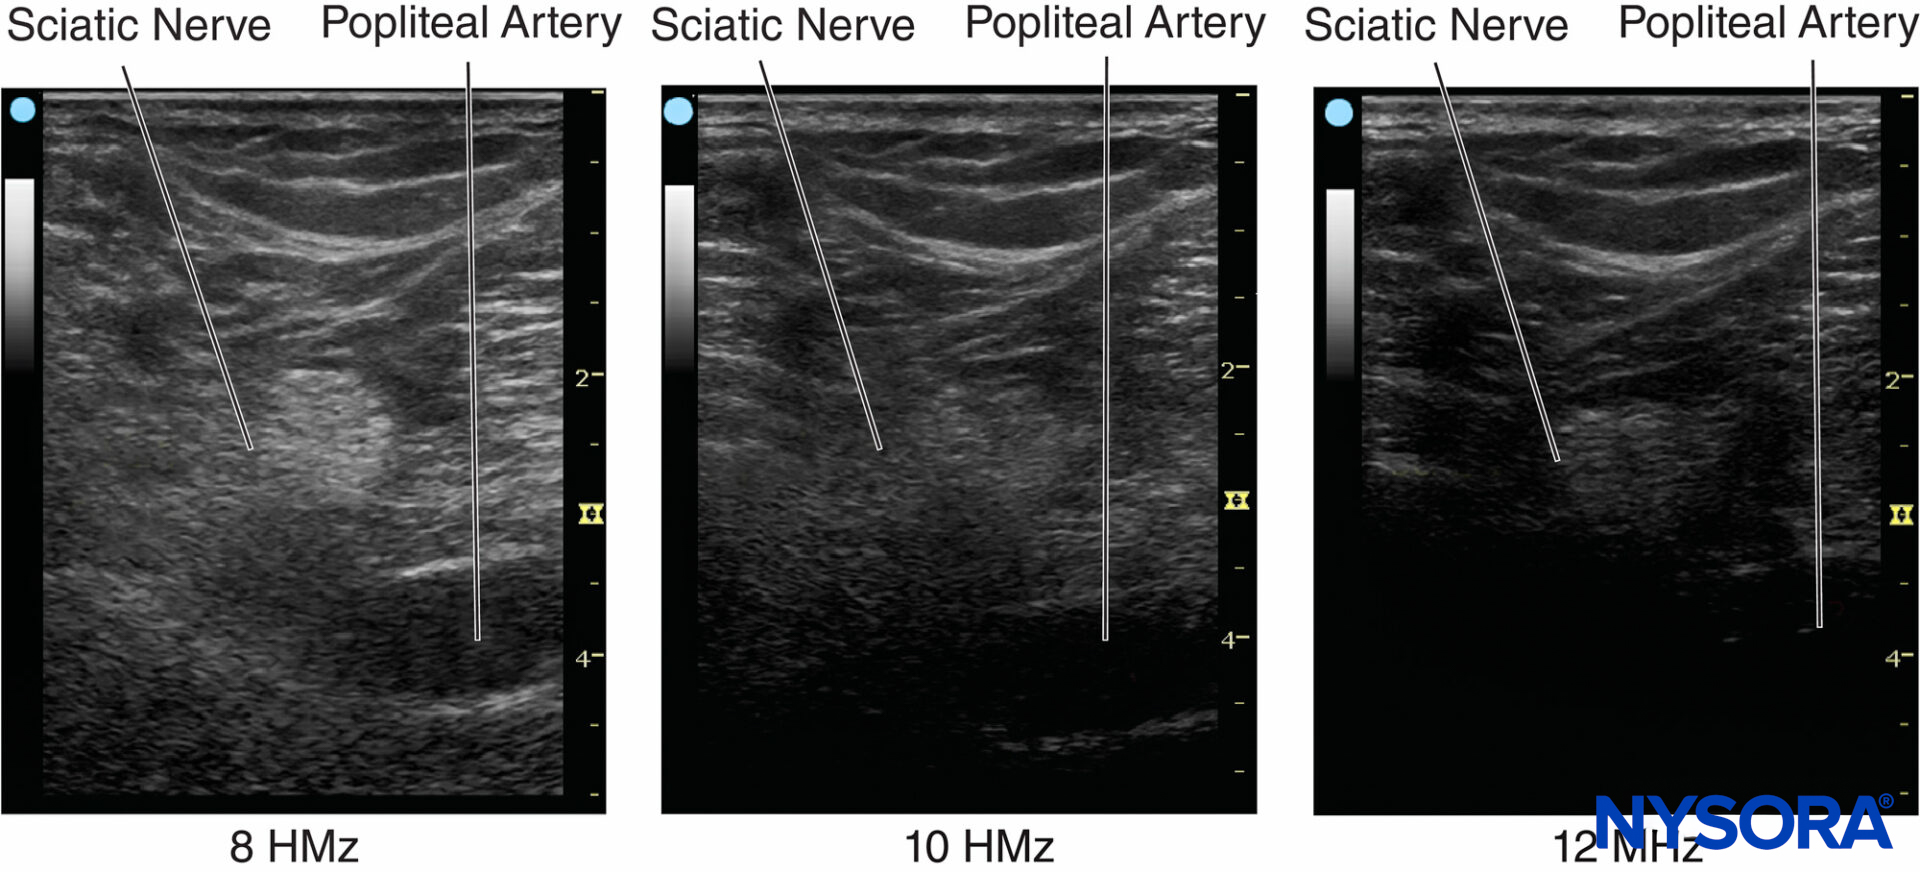

The number of cycles within a pulse is determined by the damping characteristics of the transducer. The number of cycles within a pulse is usually set between 2 and 4 by the manufacturer of the ultrasound machines. As an example, if a 2-MHz ultrasound transducer is theoretically used to do the scanning, the axial resolution would be between 0.8 and 1.6 mm, making it impossible to visualize a 21-gauge needle. For constant acoustic velocity, higher-frequency ultrasound can detect smaller objects and provide an image with better resolution. The axial resolution of current ultrasound systems is between 0.05 and 0.5 mm. Figure 5 shows images at different resolutions when a 0.5-mm diameter object is visualized with three different frequency settings.

Figure 5. Ultrasound frequency affects the resolution of the imaged object. Resolution can be improved by increasing frequency and reducing the beam width by focusing. (Reproduced with permission from Hadzic A: Hadzic’s Peripheral Nerve Blocks and Anatomy for Ultrasound-Guided Regional Anesthesia, 2nd ed. New York: McGraw-Hill, Inc; 2011.)

Lateral resolution is another parameter of sharpness to describe the minimum side-by-side distance between two objects. It is determined by both ultrasound frequency and beam width. The higher frequencies have a narrower focus and provide better axial and lateral resolution. Lateral resolution can also be improved by adjusting focus to reduce the beam width.